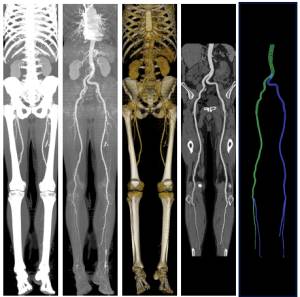

CT peripheral angiography is a diagnostic imaging procedure that uses computed tomography (CT) technology to visualize the blood vessels in the peripheral (outer) parts of